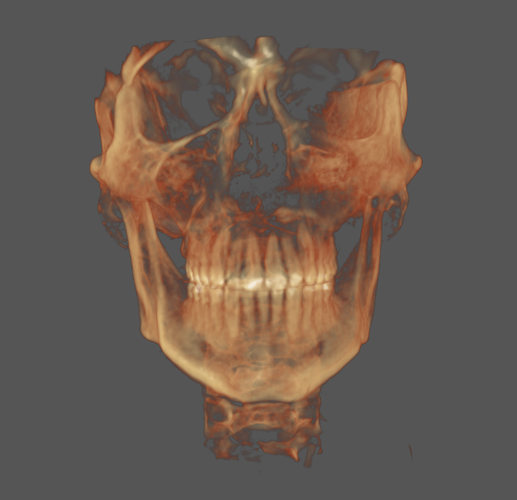

Planning on SARPE soon, too old for most ORTHO to work unfortunately.

Obviously leaning out which i am in the progress of but other than that not sure what else I can do or what my weakest features are. (My mandible is obviously recessed as is my maxilla.)